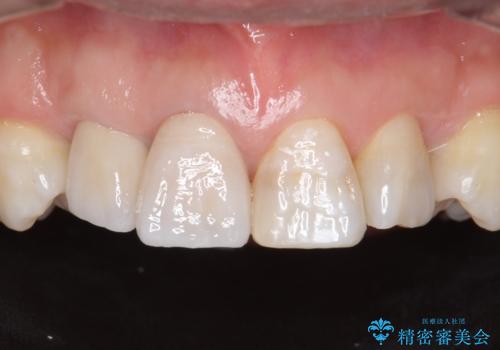

インビザライン矯正 神経のない歯をとって、全て天然歯に